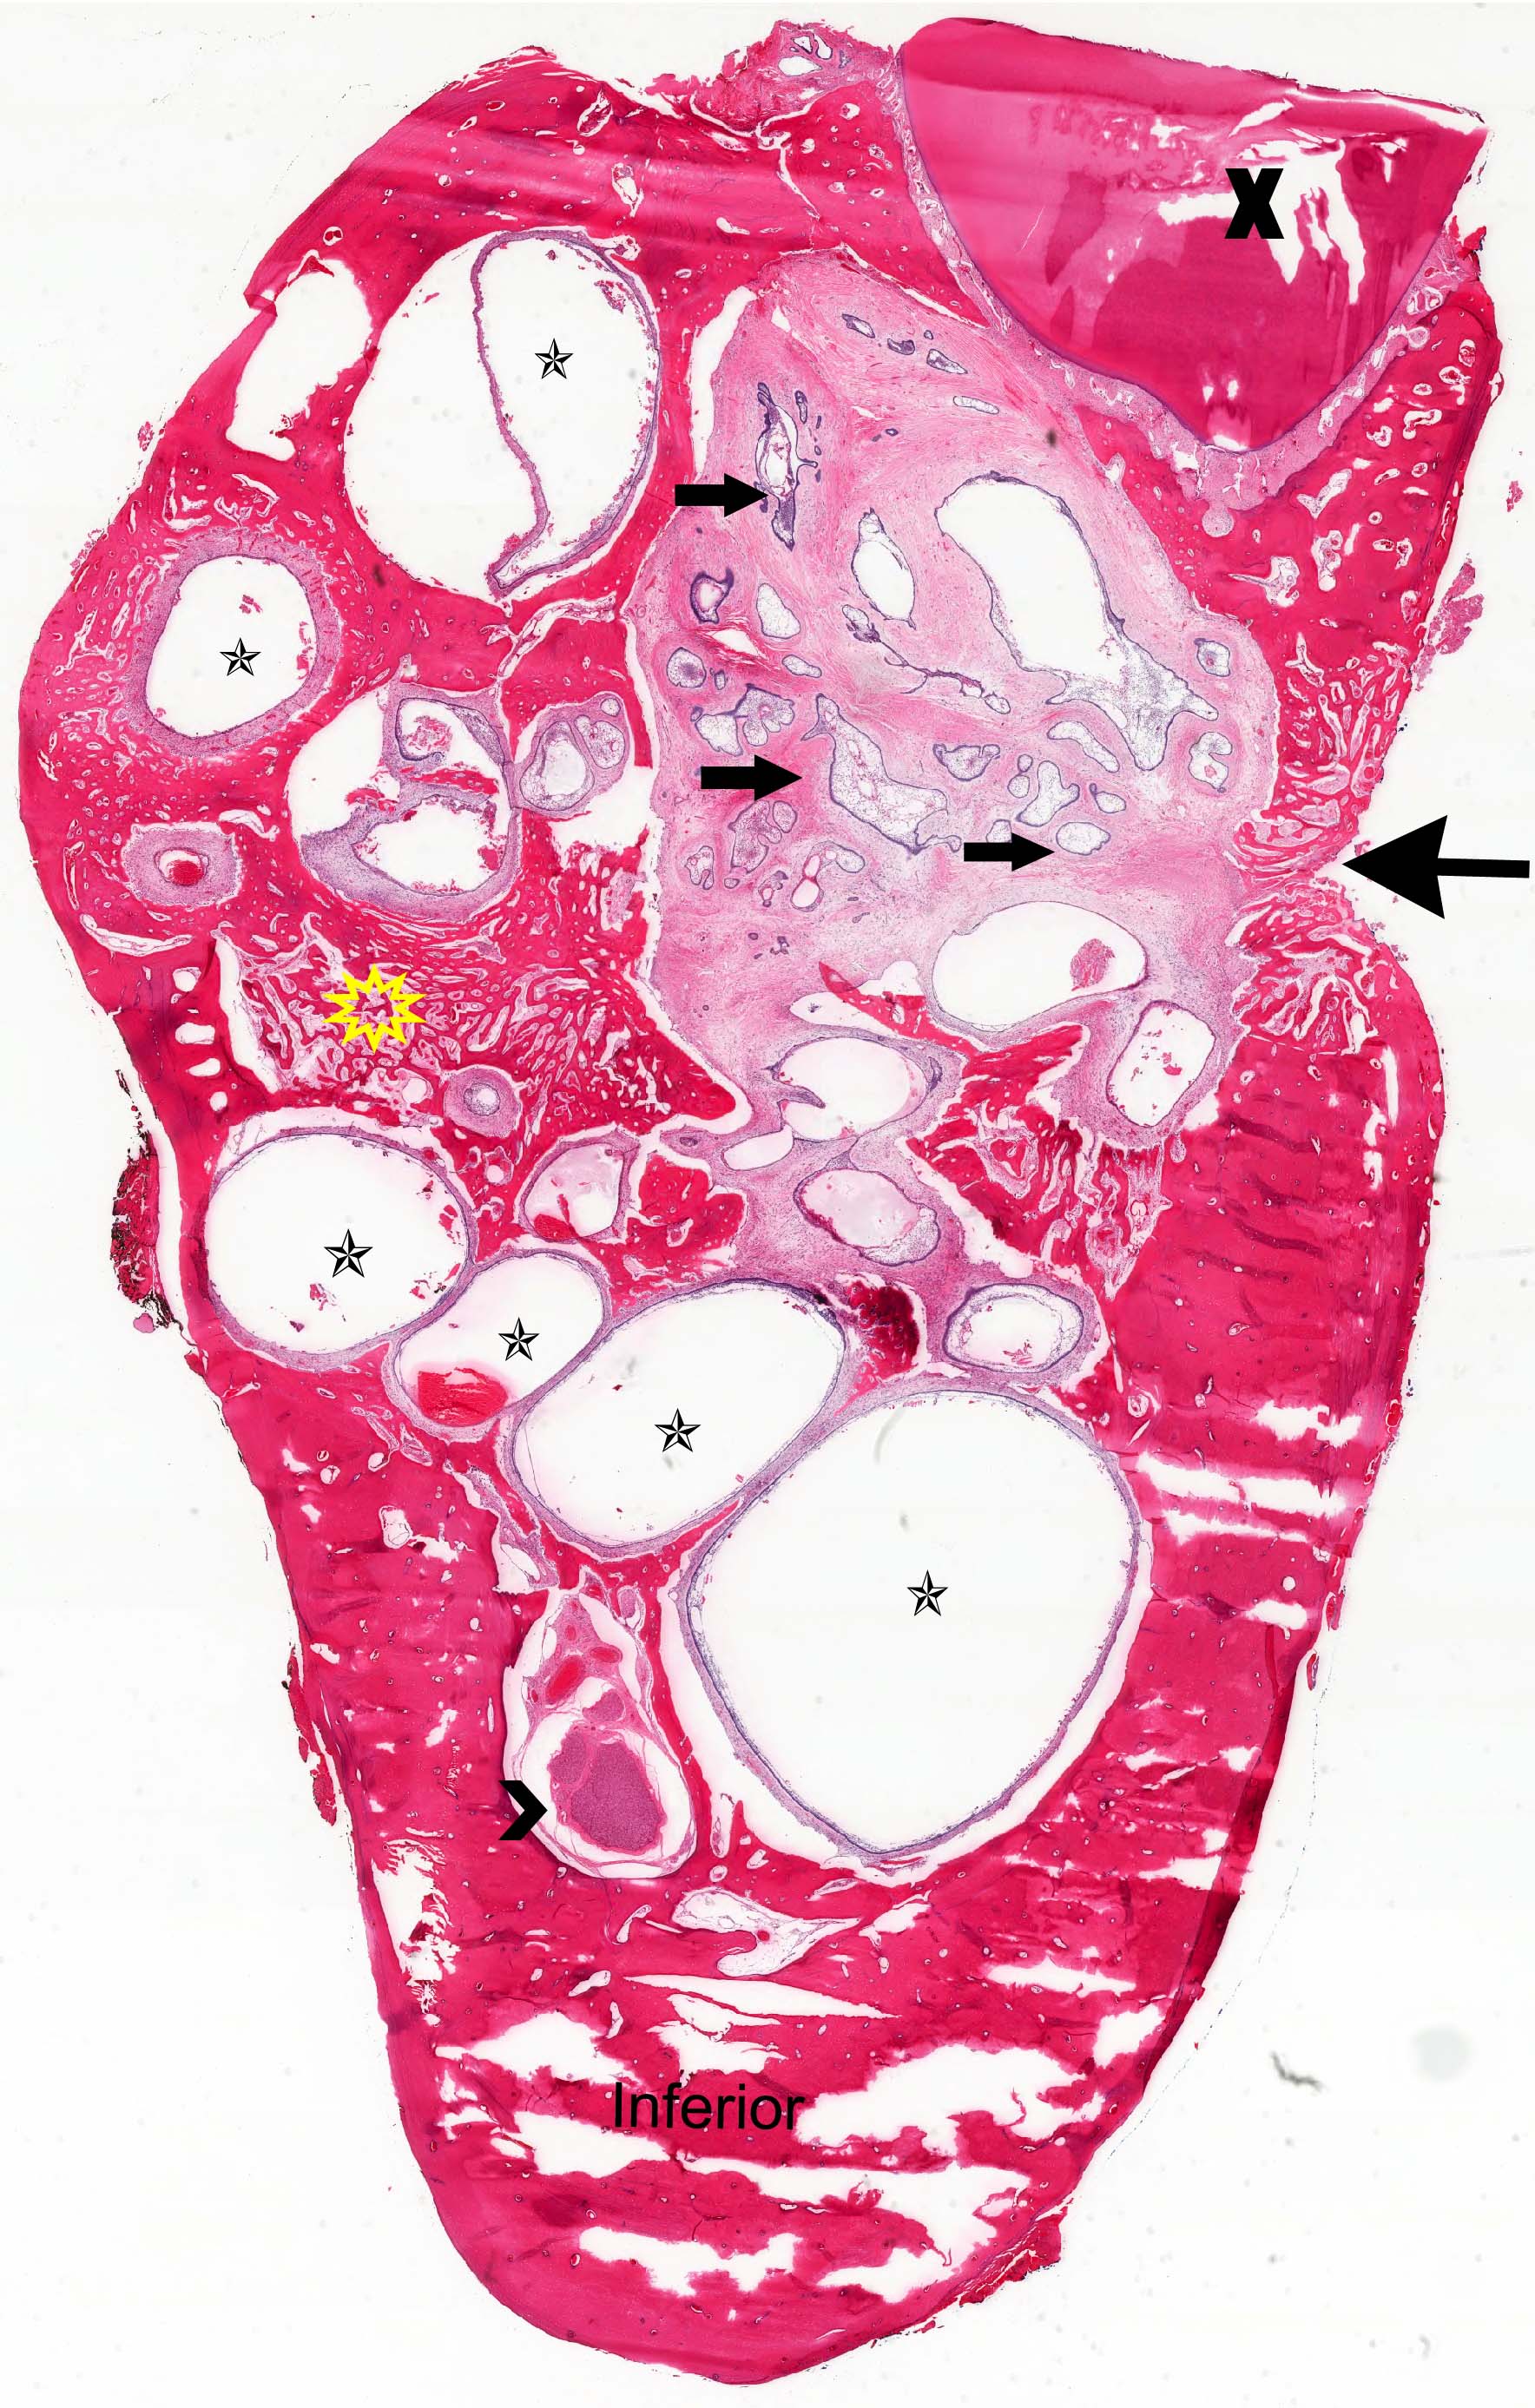

Microscopic (histologic) images

Contributed by Kelly Magliocca, D.D.S., M.P.H. and Anne C. McLean-Holden, D.M.D., M.S.

- Ameloblastoma, conventional type:

- Viscous mucoid fluid present on cut surface

- Macrocystic degeneration: larger cystic spaces, may contain clear or red-brown fluid

- Solid, multiple cystic spaces or a combination thereof

- Resorbs tooth roots

- Note expansion or extension beyond bone

- May be associated with impacted tooth

- In mandible, note relation to inferior alveolar nerve if applicable

- Ameloblastoma, unicystic type:

- When resected for margins with surrounding bone, unicystic gross appearance is conspicuous and may contain red-brown fluid

- Ameloblastoma, conventional

- Expansile multilocular radiolucency, well defined, corticated border

- Some cases exhibit classic soap bubble appearance

- May or may not be associated with impacted tooth / teeth

- Resorption or displacement of tooth roots